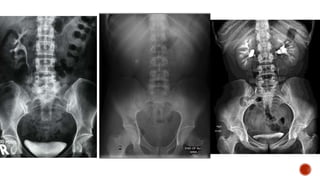

It is theradiographic examination of urinary tract including renal parenchyma, calyces and pelvis after intravenous injection of contrast media.

1. Screening ofthe entire urinary tract especially in cases of haematuria or pyuria. 2. Diseases of the renal collecting system and renal pelvis 3. Differentiation of function of both kidneys. 4. Abnormalities of the ureter. 5. Obstructive uropathy- IVU is the gold standard. 6. TB of the urinary tract 7. Calculus disease. 8. Potential Renal Donors. 9. Prior to endo-urological procedures and surgery of urinary tract. 10. Suspected renal injury. 11. Renal colic or flank pain.

1. VATER anomalies:These patients have vertebral, anal, tracheo oesophageal, and renal anomalies. Renal anomalies are seen in about 90% of patients. 2. Malformation of urinary tract, e.g., polycystic disease, PUJ obstruction etc. 3. Neurological disorders affecting urinary tract. 4. Malformation of genitalia like bilateral cryptorchidism, III degree hypospadias, family history of urinary tract anomalies, urinary tract infection. 5. Enuresis in the presence of bacteriuria,abnormal urinary sediment, adolescents, diurnal/nocturnal incontinence and history of recurrent urinary tract infection. 6. In girls with constant or intermittent dampness which suggests an ectopically inserted ureter, IVU is mandatory. 7. Anorectal anomalies.

1. Iodine sensitivity. 2.Pregnancy. 3. Severe history of anaphylaxis previously carries 30% risk of similar reaction on a subsequent occasion. The risk is lower with low osmolar contrast media. 4. Raised serum creatinine levels

• overnight fastingfor 5 hours prior to the date of examination; a laxative may not be necessary for bowel preparation as it does not improve image quality • on the day of the procedure take a scout/pilot film to check patient preparation and also to look for radiopaque calculi • check serum creatinine level to be within the normal range (as per hospital guidelines) • take a history of the patient for any known drug allergies followed by written informed consent for the procedure • emergency medications and emergency equipment must always be available in case the patient has a reaction to contrast